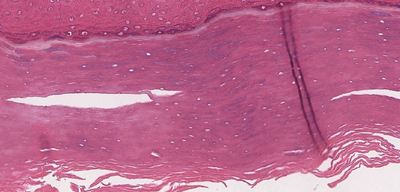

Question 1

Question

escoje la opcion correcta

Image:

8ba5d953-89e2-4f75-9725-b506f32ec872.JPG (image/JPG)

Answer

epitelio plano estratificado no queratinzaddo

epitelio plano estratificado queratinizado

epitelio pseudoestratificado cilindrico ciliado con celulas caliciformes

urotelio

epitelio plano simple